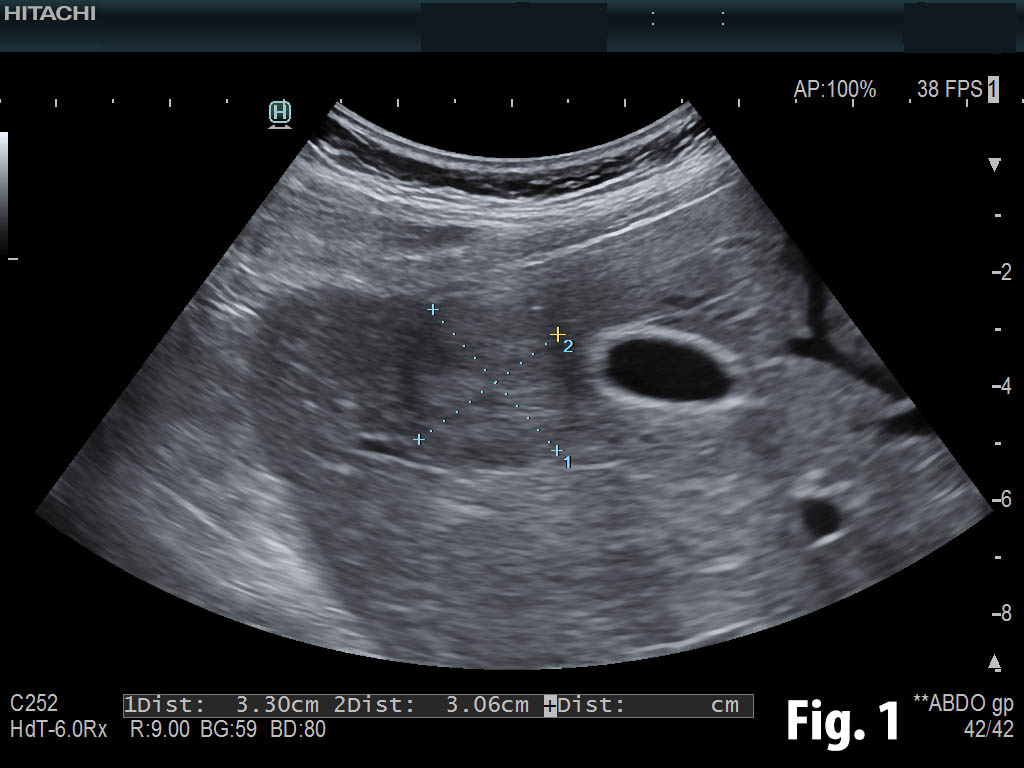

Student Image Challenge #74

The following characteristic flow on color Doppler and typical CEUS pattern are suggestive of.. ?

Case courtesy of Prof Adrian Săftoiu